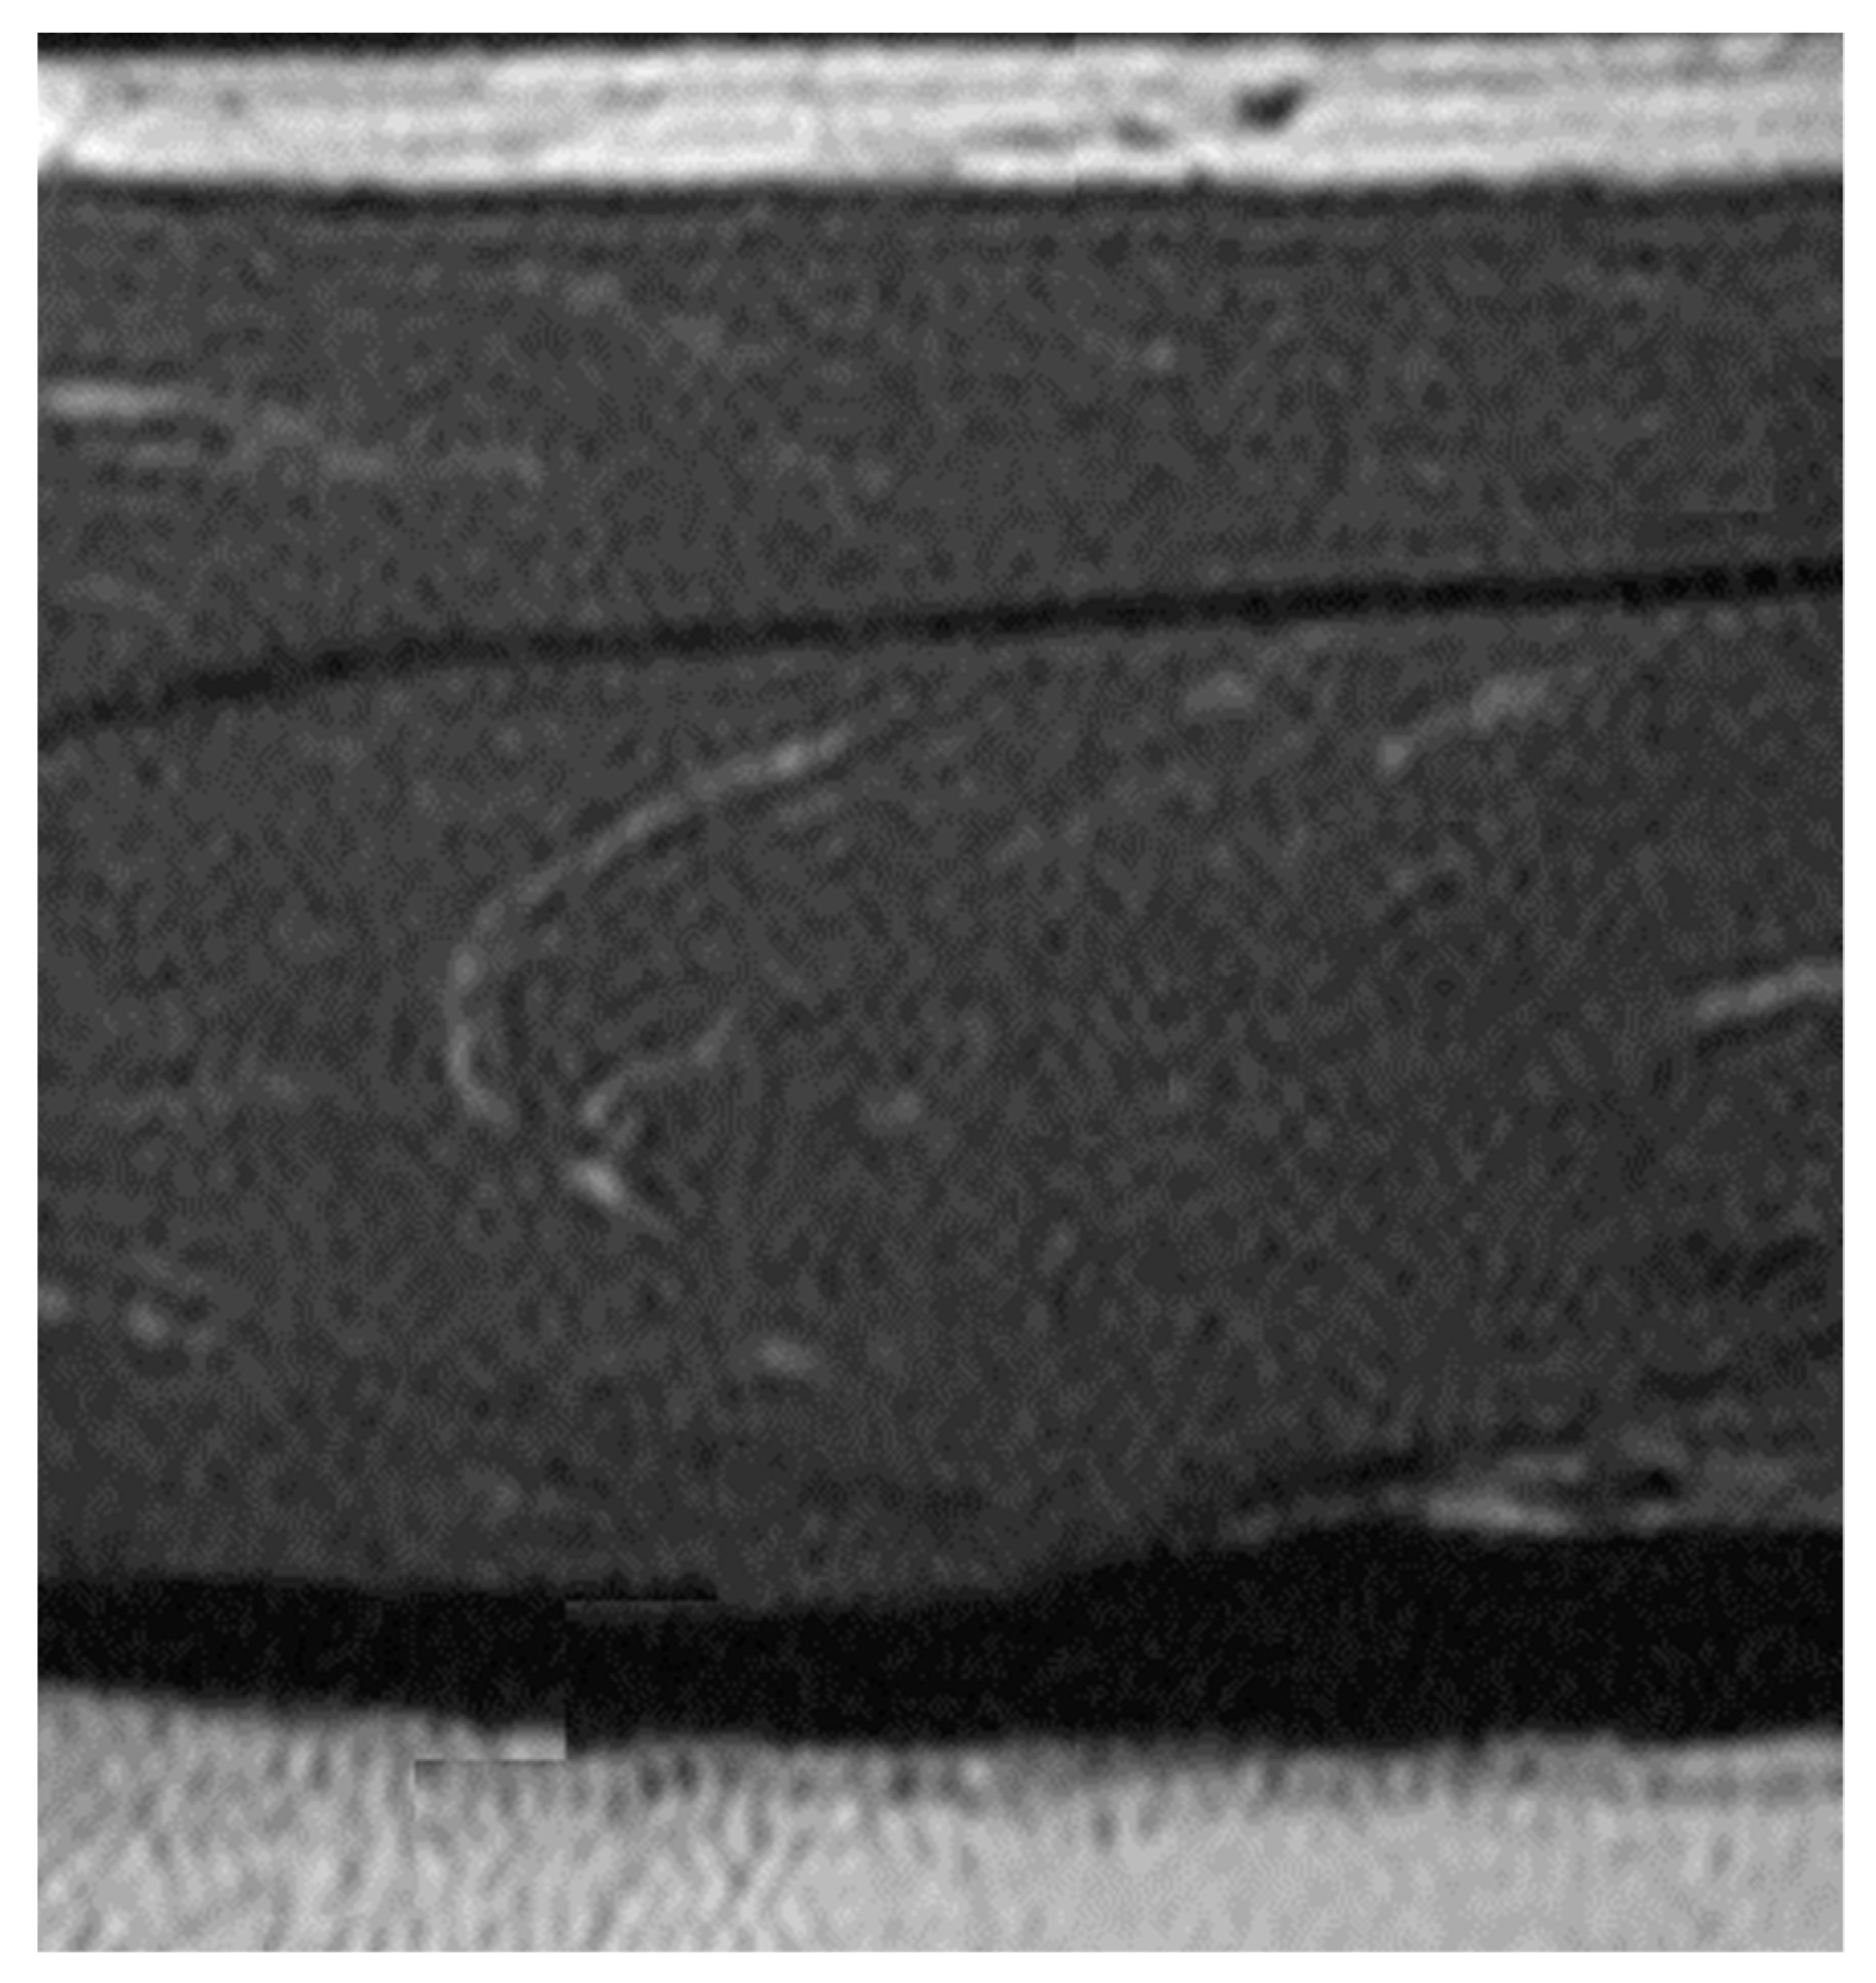

2.3. Measurement Method of Sound Velocity in Human Crus

3.1. Experimental Results of the Measurement of Sound Velocity in Human Crus